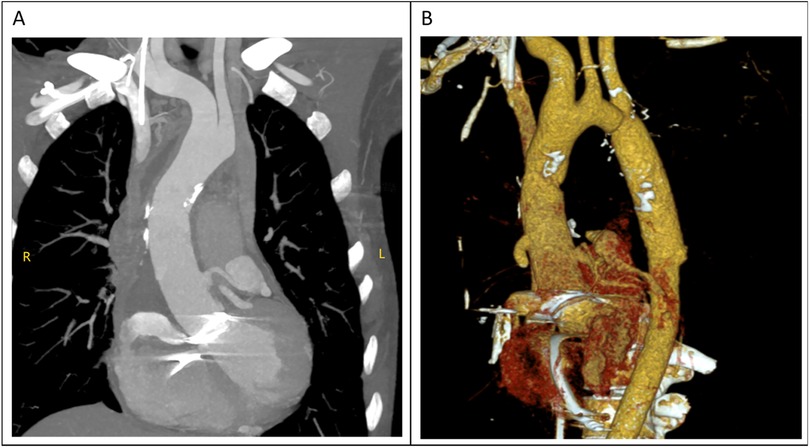

The total surgical time was 4 h and 25 min, with a cardiopulmonary bypass time of 143 min and an aortic cross-clamp time of 78 min. The tracheal tube was removed 13 h postoperatively. However, the patient began to experience frequent episodes of cardiac arrest lasting 5–10 s during the 20th and 25th hours postoperatively, for a total of 12 episodes, all of which reversed spontaneously. The cardiac conduction tissue was suspected to be damaged or affected by edema. An emergency temporary pacing device was implanted, and no further episodes of cardiac arrest occurred; her condition remained stable. Postoperative CTA scan showed satisfactory revision results (Figures 4A,B), and the postoperative echocardiogram demonstrated normal valve function. The patient was discharged on the ninth postoperative day.

Figure 4

(A,B) the diameter of the ascending aorta had returned to normal in the computed tomography (CT) examination performed after surgery.